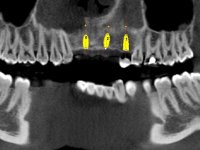

Foi aconselhada a extracção dos dentes 12 e 11 e esperar mais 3 meses para se conseguir uma completa cicatrização da zona. Estabilizada a situação fazer-se –ia um enceramento de diagnóstico que dando origem a uma guia imagiológica permitiria fazer uma TAC. em que o posicionamento idealizado dos dentes pudesse ser relacionado com o património ósseo. O objectivo seria fazer uma ponte cerâmica implanto suportada.

O paciente foi observado conjuntamente e a dúvida que surgiu de imediato foi se seria possível com a regeneração óssea a efectuar poder ser reabilitada naturalmente a zona das papilas interdentárias. Nesse sentido foi feito um enceramento de diagnóstico que contemplaria as duas hipóteses, utilizando ou não a cerâmica gengival. A confecção desse enceramento foi fundamental para expor ao paciente a dificuldade da reabilitação. O wax-up deu origem a um mock-up que foi aprovado pelo paciente e que simultaneamente serviu de guia imagiológica. O caso foi planificado cirurgicamente e realizada uma guia cirúrgica com que foram colocados os implantes. Após 10 semanas foi feita a 1ª impressão para confecção da ponte provisória. Foram criados os primeiros perfis de emergência na gengiva artificial e foi digitalizado o modelo. Por processo de CAD-CAM foi confeccionada uma ponte provisória aparafusada baseada no enceramento de diagnóstico. A ponte trabalhou durante 8 semanas os tecidos moles que foram fielmente copiados numa impressão com técnica de moldeira aberta. Os transferes foram individualizados com resina composta para copiarem fielmente os perfis de emergência criados pela ponte provisória. Confeccionado o modelo de trabalho definitivo, foi realizada uma infra-estrutura em zircónio seguindo a orientação do enceramento de diagnóstico. O assentamento da infra-estrutura foi testado em boca e simultaneamente foi novamente impressionados os tecidos moles com um silicone fluido. Nessa consulta foi feito o levantamento da cor. Os dentes 13 e 23 apresentavam uma saturação anormalmente forte que resolvemos não valorizar, optando por privilegiar a relação com o sector antero-inferior. Foi realizada uma nova gengiva artificial com a impressão que acompanhou a impressão de arrasto com a infra-estrutura. Após a colocação da cerâmica na infra-estrutura foram coladas as meso-estruturas. O trabalho final foi aparafusado lentamente permitindo a adaptação dos tecidos moles.